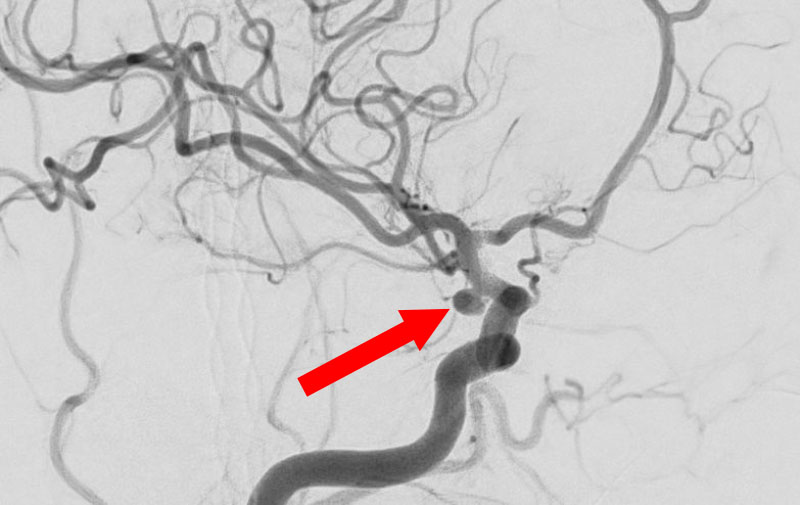

'25年10月

くも膜下出血

右内頚動脈脳動脈瘤破裂

40代

救急外来

No.1592 手術前

No.1592 手術中

No.1592 手術後